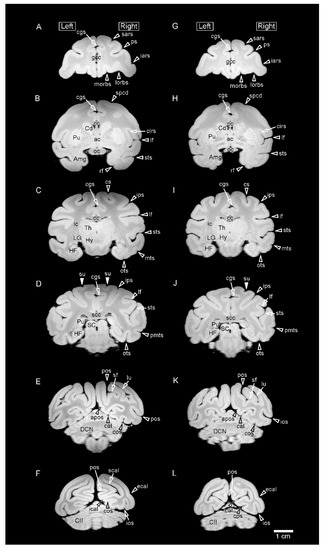

3.1. MR Images and 3D-Rendered Images

3.2. MRI-Based Morphometry